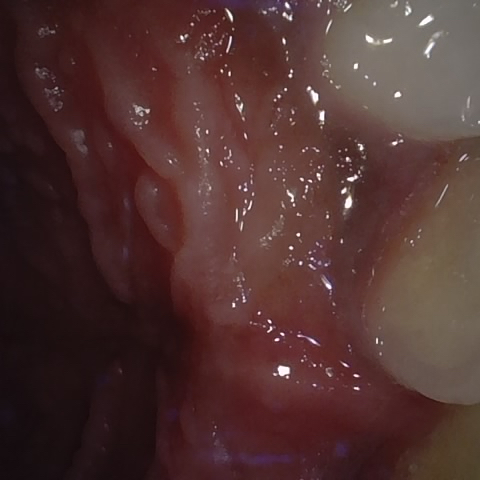

Annotated as "Good"

Original Image Rendering Image